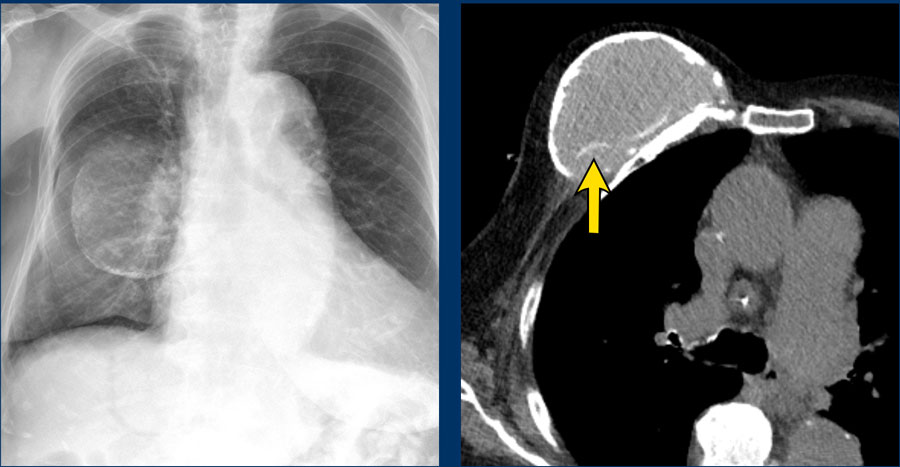

Breast implant ruptured